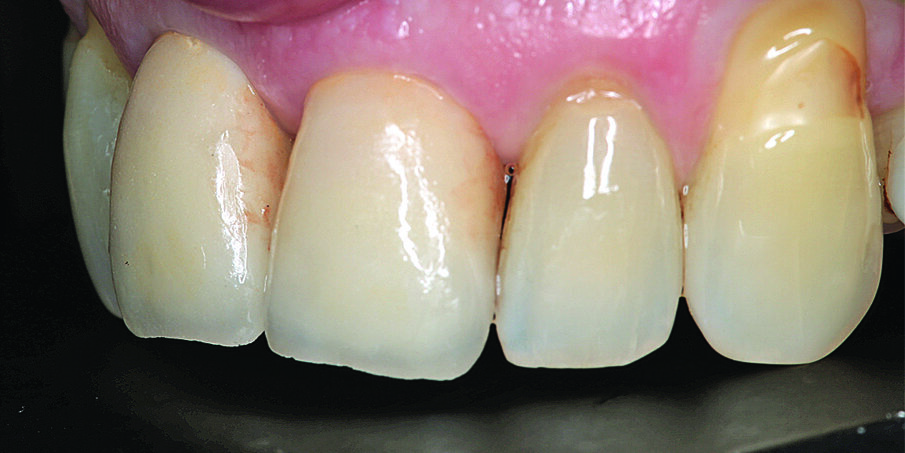

Dva mjeseca nakon implantacije uzet je otisak. Periimplantatno meko tkivo bilo je bez upale s lijepim izlaznim profilom. Fragment zuba jasno se vidi na pojedinačnoj rendgenskoj snimci, a razina interdentalne kosti i površina implantata ne ukazuju ni na kakve patološke promjene. Implantati su se stabilno oseointegrirali (Slika 10.). Otisak na implantatima uzet je materijalima Impregum™ (3M™ ESPE™), Permadyne™ (3M™ ESPE™) i individualnom žlicom za otiske. Kao definitivna opskrba dva mjeseca nakon implantacije izrađene su pojedinačne krunice od potpuno obložene cirkonij-oksidne keramike na titanijskim bazama (Slike 11. i 12.).

Slike 11 i 12. Definitivna protetska opskrba zubi 11 i 21: cirkonij-oksidne krunice na titanijskim bazama.